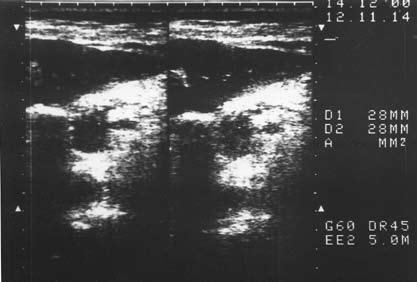

Ультразвуковое исследование (сканирование) является одним из наиболее информативных и притом неинвазивных методов исследования ПЖ и должно осуществляться во всех случаях, когда подозревается ее патология (рис. 137–139).

Датчик располагается в эпигастральной области и его перемещают соответственно проекции железы на области левого и правого подреберий. В норме ПЖ имеет ровные, четкие контуры и гомогенную структуру, а диаметр главного панкреатического протока не превышает 1,5–2 мм. При патологии может выявляться общее увеличение размеров органа с равномерным уменьшением эхоплотности, свидетельствующее об отеке. Уменьшение размеров железы, неоднородность структуры, наличие мелких участков уплотнения ткани, а также нечеткость контуров могут говорить о фиброзных изменениях в железе, а небольшие резко выраженные эхоположительные узелки – об очаговом обызвествлении паренхимы. Эхоструктуры высокой плотности, расположенные в протоке и дающие феномен «ультразвуковой дорожки», являются признаком внутрипротоковых конкрементов. Жидкостные образования (ложные кисты, вялотекущие абсцессы) представляются на эхограмме округлыми участками значительно пониженной эхоплотности с более или менее четкими контурами и дорсальным усилением. Хорошо сформированные ложные кисты с жидким содержимым имеют округлую или овальную форму, гомогенны и окружены четко выраженной капсулой. Содержимое несформировавшихся кист и абсцессов может быть неоднородным из‑за наличия в них, помимо жидкости, тканевых секвестров и детрита.

Рис. 139. Хронический панкреатит. Конкремент в просвете протока ПЖ (DP)